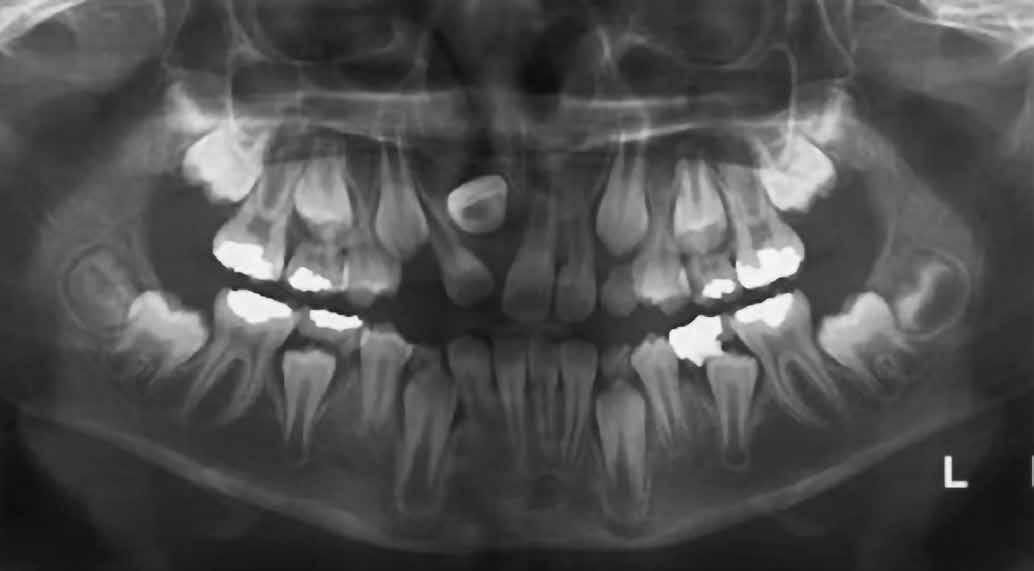

A 10 éves férfi páciens a felső frontfogai késői/nem megvalósuló előtörése miatt kereste fel a rendelőnket. A klinikai és a radiológiai vizsgálat során a jobb felső nagymetszőfog impakcióját észleltük (1. ábra). A fog horizontális tengelyállással és dilacerált gyökérrel rendelkezett. A felső dentális középvonal a fogak vándorlása miatt jelentős mértékben elcsúszott. A bal felső kismetszőfog is rendkívül kedvezőtlen pozícióba került.

Dr. Kazem Dalaie, dr. Samin Ghaffari, dr. Mazir Mir (Irán, Németország) 1. a ábra: Az intraorális felvételen jól látható a jobb felső nagymetszőfog lehetséges impakciójára utaló foghiány.

1. b ábra: A panoráma röntgenfelvételen megfigyelhető a teljes impakcióban lévő jobb felső nagymetszőfog. 1. c ábra: A CBCT felvétel is igazolja a jobb felső nagymetszőfog impakcióját.